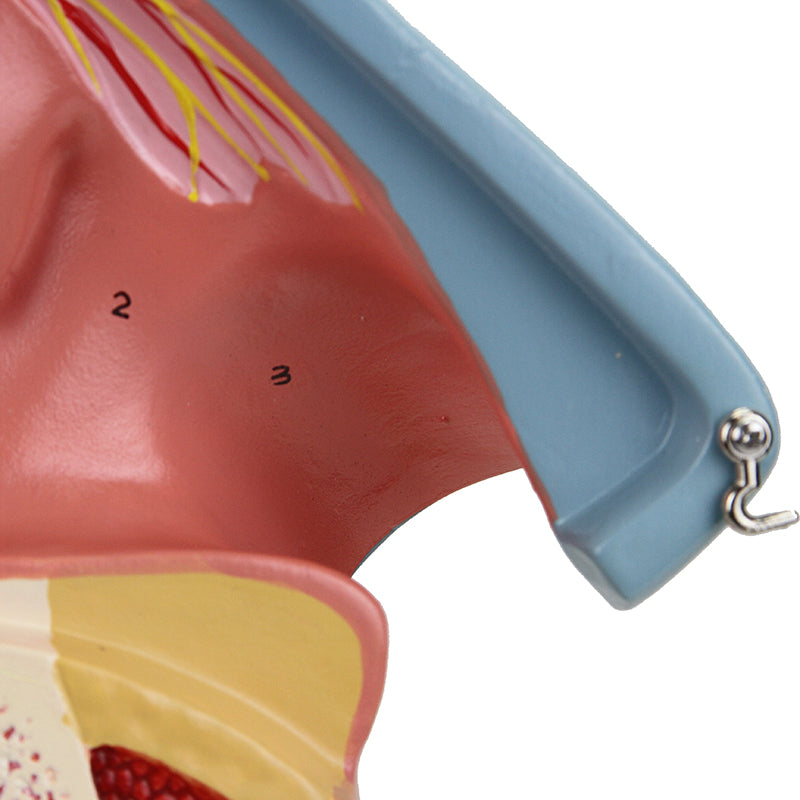

鼻腔模型,放大三倍,三部分組成

此模型為實物三倍大小,展示鼻腔的中間剖面。鼻中隔及部分嗅覺上皮可拆卸,以顯示深層內部結構。重要解剖結構均有編號;採用耐用合成材料製成。配合擴增實境的互動式三維解剖模型,是促進學習與輔助教學的絕佳工具。此平台讓學生能進行解剖模型的比較分析,對比各器官的結構差異。此計畫亦提供持續教育的平台,為所有學生提供機會,增進對解剖學、生理學及病理生理學的認識。

鼻腔模型,放大三倍,三部分組成

此模型為實物三倍大小,展示鼻腔的中間剖面。鼻中隔及部分嗅覺上皮可拆卸,以顯示深層內部結構。重要解剖結構均有編號;採用耐用合成材料製成。配合擴增實境的互動式三維解剖模型,是促進學習與輔助教學的絕佳工具。此平台讓學生能進行解剖模型的比較分析,對比各器官的結構差異。此計畫亦提供持續教育的平台,為所有學生提供機會,增進對解剖學、生理學及病理生理學的認識。